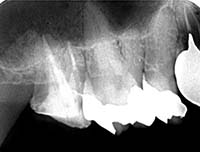

CT撮影で根の状態を“立体的”に診断

レントゲンは2Dですが、CT(3D)では病変の広がり・分岐・湾曲・破折線を正確に把握できます。

特に、

- 他院で治らなかった根尖病変

- 大臼歯の複雑な形態

- 器具破折の有無

- 嚢胞の存在

などはCTでしか判断できません。“診断の精度=治療の成功率” であるため、CT診断は必須です。